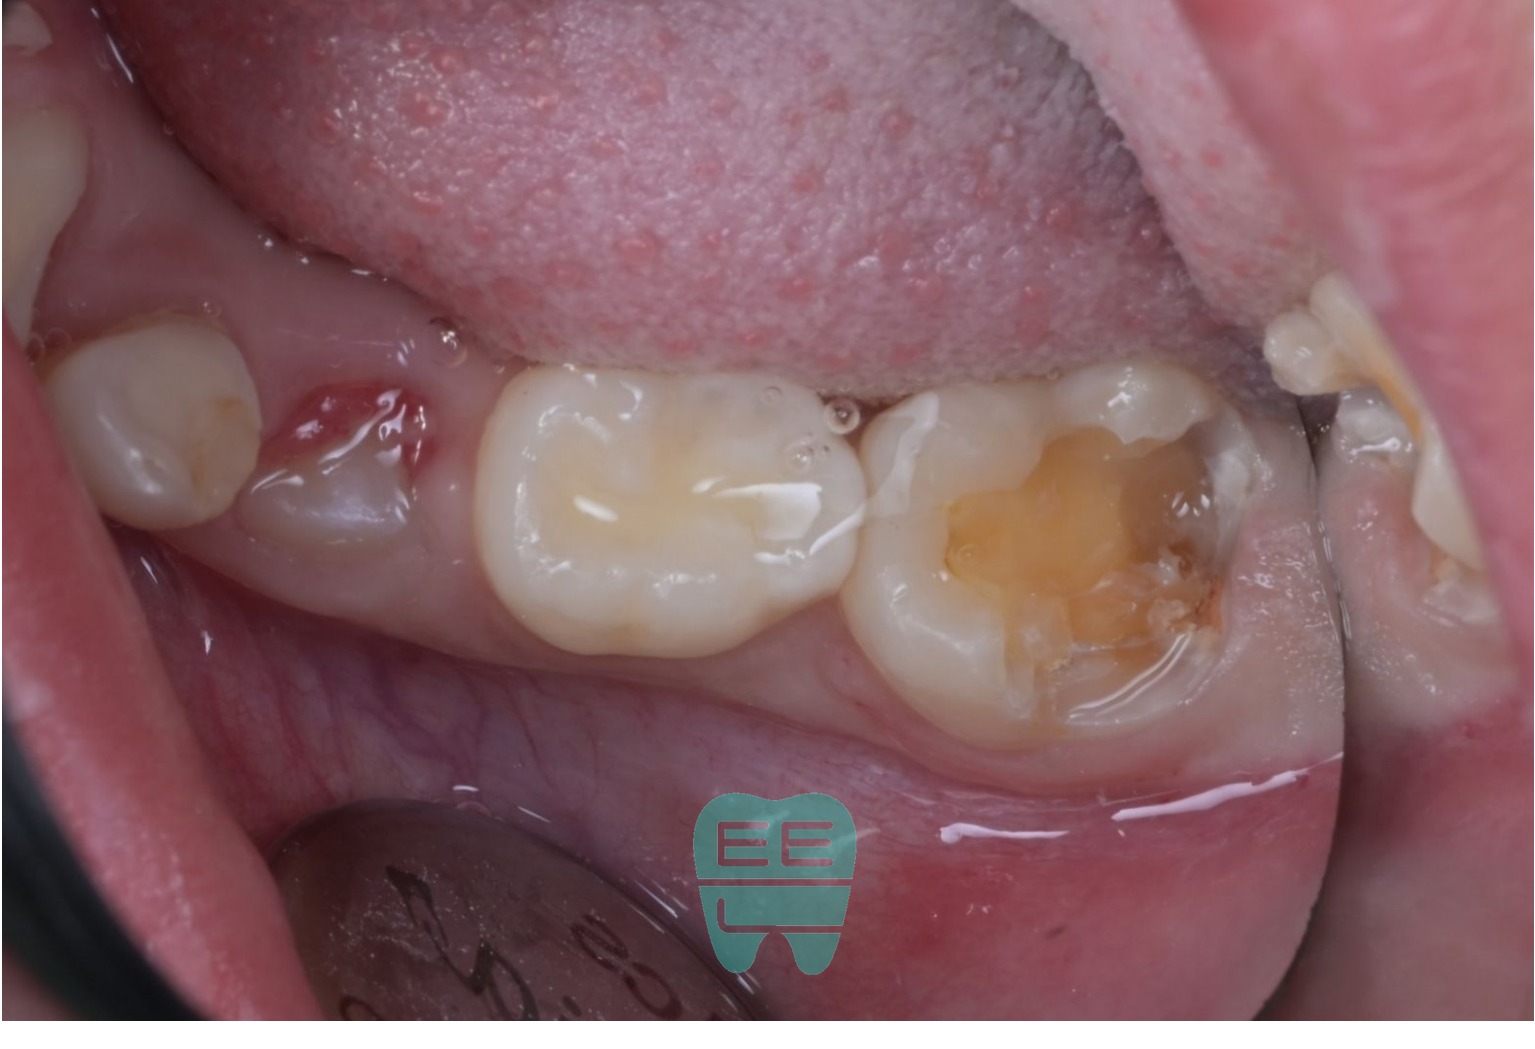

3. 기존 레진 제거: 예상보다 심각한 2차우식

기존 레진을 제거하는데, 접착이 제대로 되어있지 않아 톡 하고 탈락해버렸습니다. 그 아래로 드러난 것은 하방 2차우식과 잇몸 아래까지 파고든 치은연하 우식이었습니다.

러버댐을 제대로 장착하려면, 잇몸 아래까지 내려간 충치 부위의 잇몸 정리(치은절제)가 먼저 필요한 상황이었습니다.